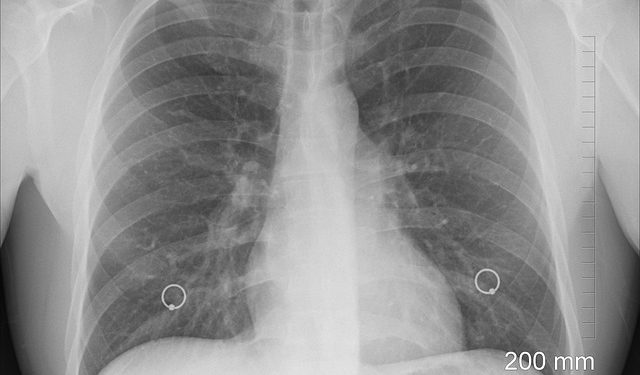

paru-paru sehat

(Ilustrasi.Pixabay)

Namun, arti dari spekulasi tersebut kurang tepat, melainkan adanya bercak putih di paru-paru, yang dikenal sebagai infiltrat.

Untuk menentukan apakah seseorang memiliki paru-paru yang terkontaminasi, diperlukan pemeriksaan medis seperti rontgen atau foto thorax.

Kasus seperti tersebut, disarankan segera melakukan pemeriksaan lebih lanjut melalui rontgen atau foto thorax sangat untuk mengetahui apakah ada infiltrat di paru-paru.